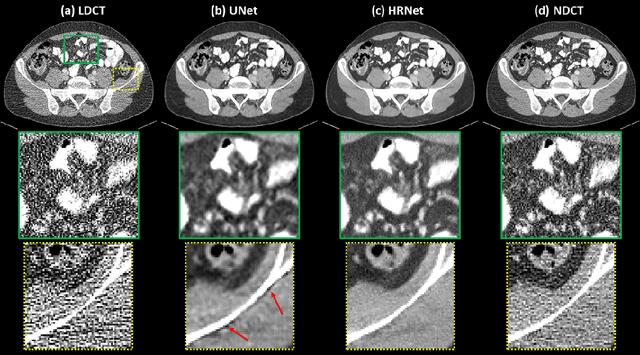

Abstract:Low Dose Computed Tomography (LDCT) is clinically desirable due to the reduced radiation to patients. However, the quality of LDCT images is often sub-optimal because of the inevitable strong quantum noise. Inspired by their unprecedent success in computer vision, deep learning (DL)-based techniques have been used for LDCT denoising. Despite the promising noise removal ability of DL models, people have observed that the resolution of the DL-denoised images is compromised, decreasing their clinical value. Aiming at relieving this problem, in this work, we developed a more effective denoiser by introducing a high-resolution network (HRNet). Since HRNet consists of multiple branches of subnetworks to extract multiscale features which are later fused together, the quality of the generated features can be substantially enhanced, leading to improved denoising performance. Experimental results demonstrated that the introduced HRNet-based denoiser outperforms the benchmarked UNet-based denoiser in terms of superior image resolution preservation ability while comparable, if not better, noise suppression ability. Quantitative metrics in terms of root-mean-squared-errors (RMSE)/structure similarity index (SSIM) showed that the HRNet-based denoiser can improve the values from 113.80/0.550 (LDCT) to 55.24/0.745 (HRNet), in comparison to 59.87/0.712 for the UNet-based denoiser.